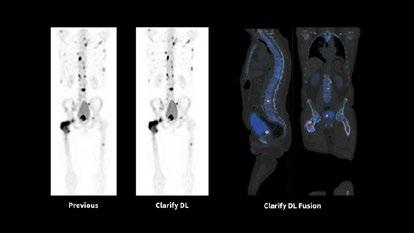

INTRODUCTION: Nuclear medicine imaging plays a pivotal role in evaluating complex prosthetic joint cases, particularly when conventional modalities are compromised by metal artifacts and nonspecific findings. This case study illustrates how the combined use of Gallium-67 scintigraphy and FDG PET imaging guided surgical intervention and evaluated disease progression with superior diagnostic sensitivity

CLINICAL PRESENTATION: A 61-year-old military veteran with a right total knee replacement presented with several months of knee swelling and severe pain. Initial evaluations including CT, bone scan, XR, ultrasound with fluid aspiration and MRI were inconclusive due to metallic artifacts and complex prosthetic fractures with adjacent oedema. The patient subsequently underwent Gallium-67 scintigraphy following an intravenous injection of 150 MBq Gallium-67 citrate, with imaging performed 48 hours later using a GE Discovery 670 system. The Gallium-67 scan demonstrated a significantly abnormal periprosthetic uptake, consistent with clinical concerns for infection. This result expediated surgical intervention and tissue biopsy of the affected area. The biopsy results revealed an extremely rare form of Diffuse Large B-cell Lymphoma involving the joint prosthesis. An FDG PET scan was then performed on a GE Omni PET system which revealed intense metabolic activity within the right knee and left knee, subcutaneous upper back activity and an FDG-avid right iliac fossa lymph node, suggesting systemic involvement. The patient underwent 6 cycles of R-CHOP and is awaiting further surgical intervention for the affected knee.

DISCUSSION: Prosthetic joint-associated lymphoma is an exceedingly rare phenomenon, with fewer than 20 cases documented in the global literature. The utility of 67Ga in lymphoma diagnosis is historically well demonstrated and this case underscores the complementary value of Gallium-67 scintigraphy and FDG PET imaging in complex prosthetic joint scenarios. While traditional imaging modalities were hampered by metal-induced artifacts and non-specific findings, nuclear medicine techniques facilitated the critical differentiation between infection and malignancy. This case also highlighted the importance of evaluating 67Ga-citrate imaging in complex clinical presentations with a comprehensive understanding of the mechanism of uptake in relevant pathologies The integrated imaging approach not only prompted surgical management but also informed systemic treatment planning, highlighting the evolving role of nuclear medicine in addressing challenging diagnostic dilemmas

Figure 1. 67Ga-citrate scan

Shimadzu Award